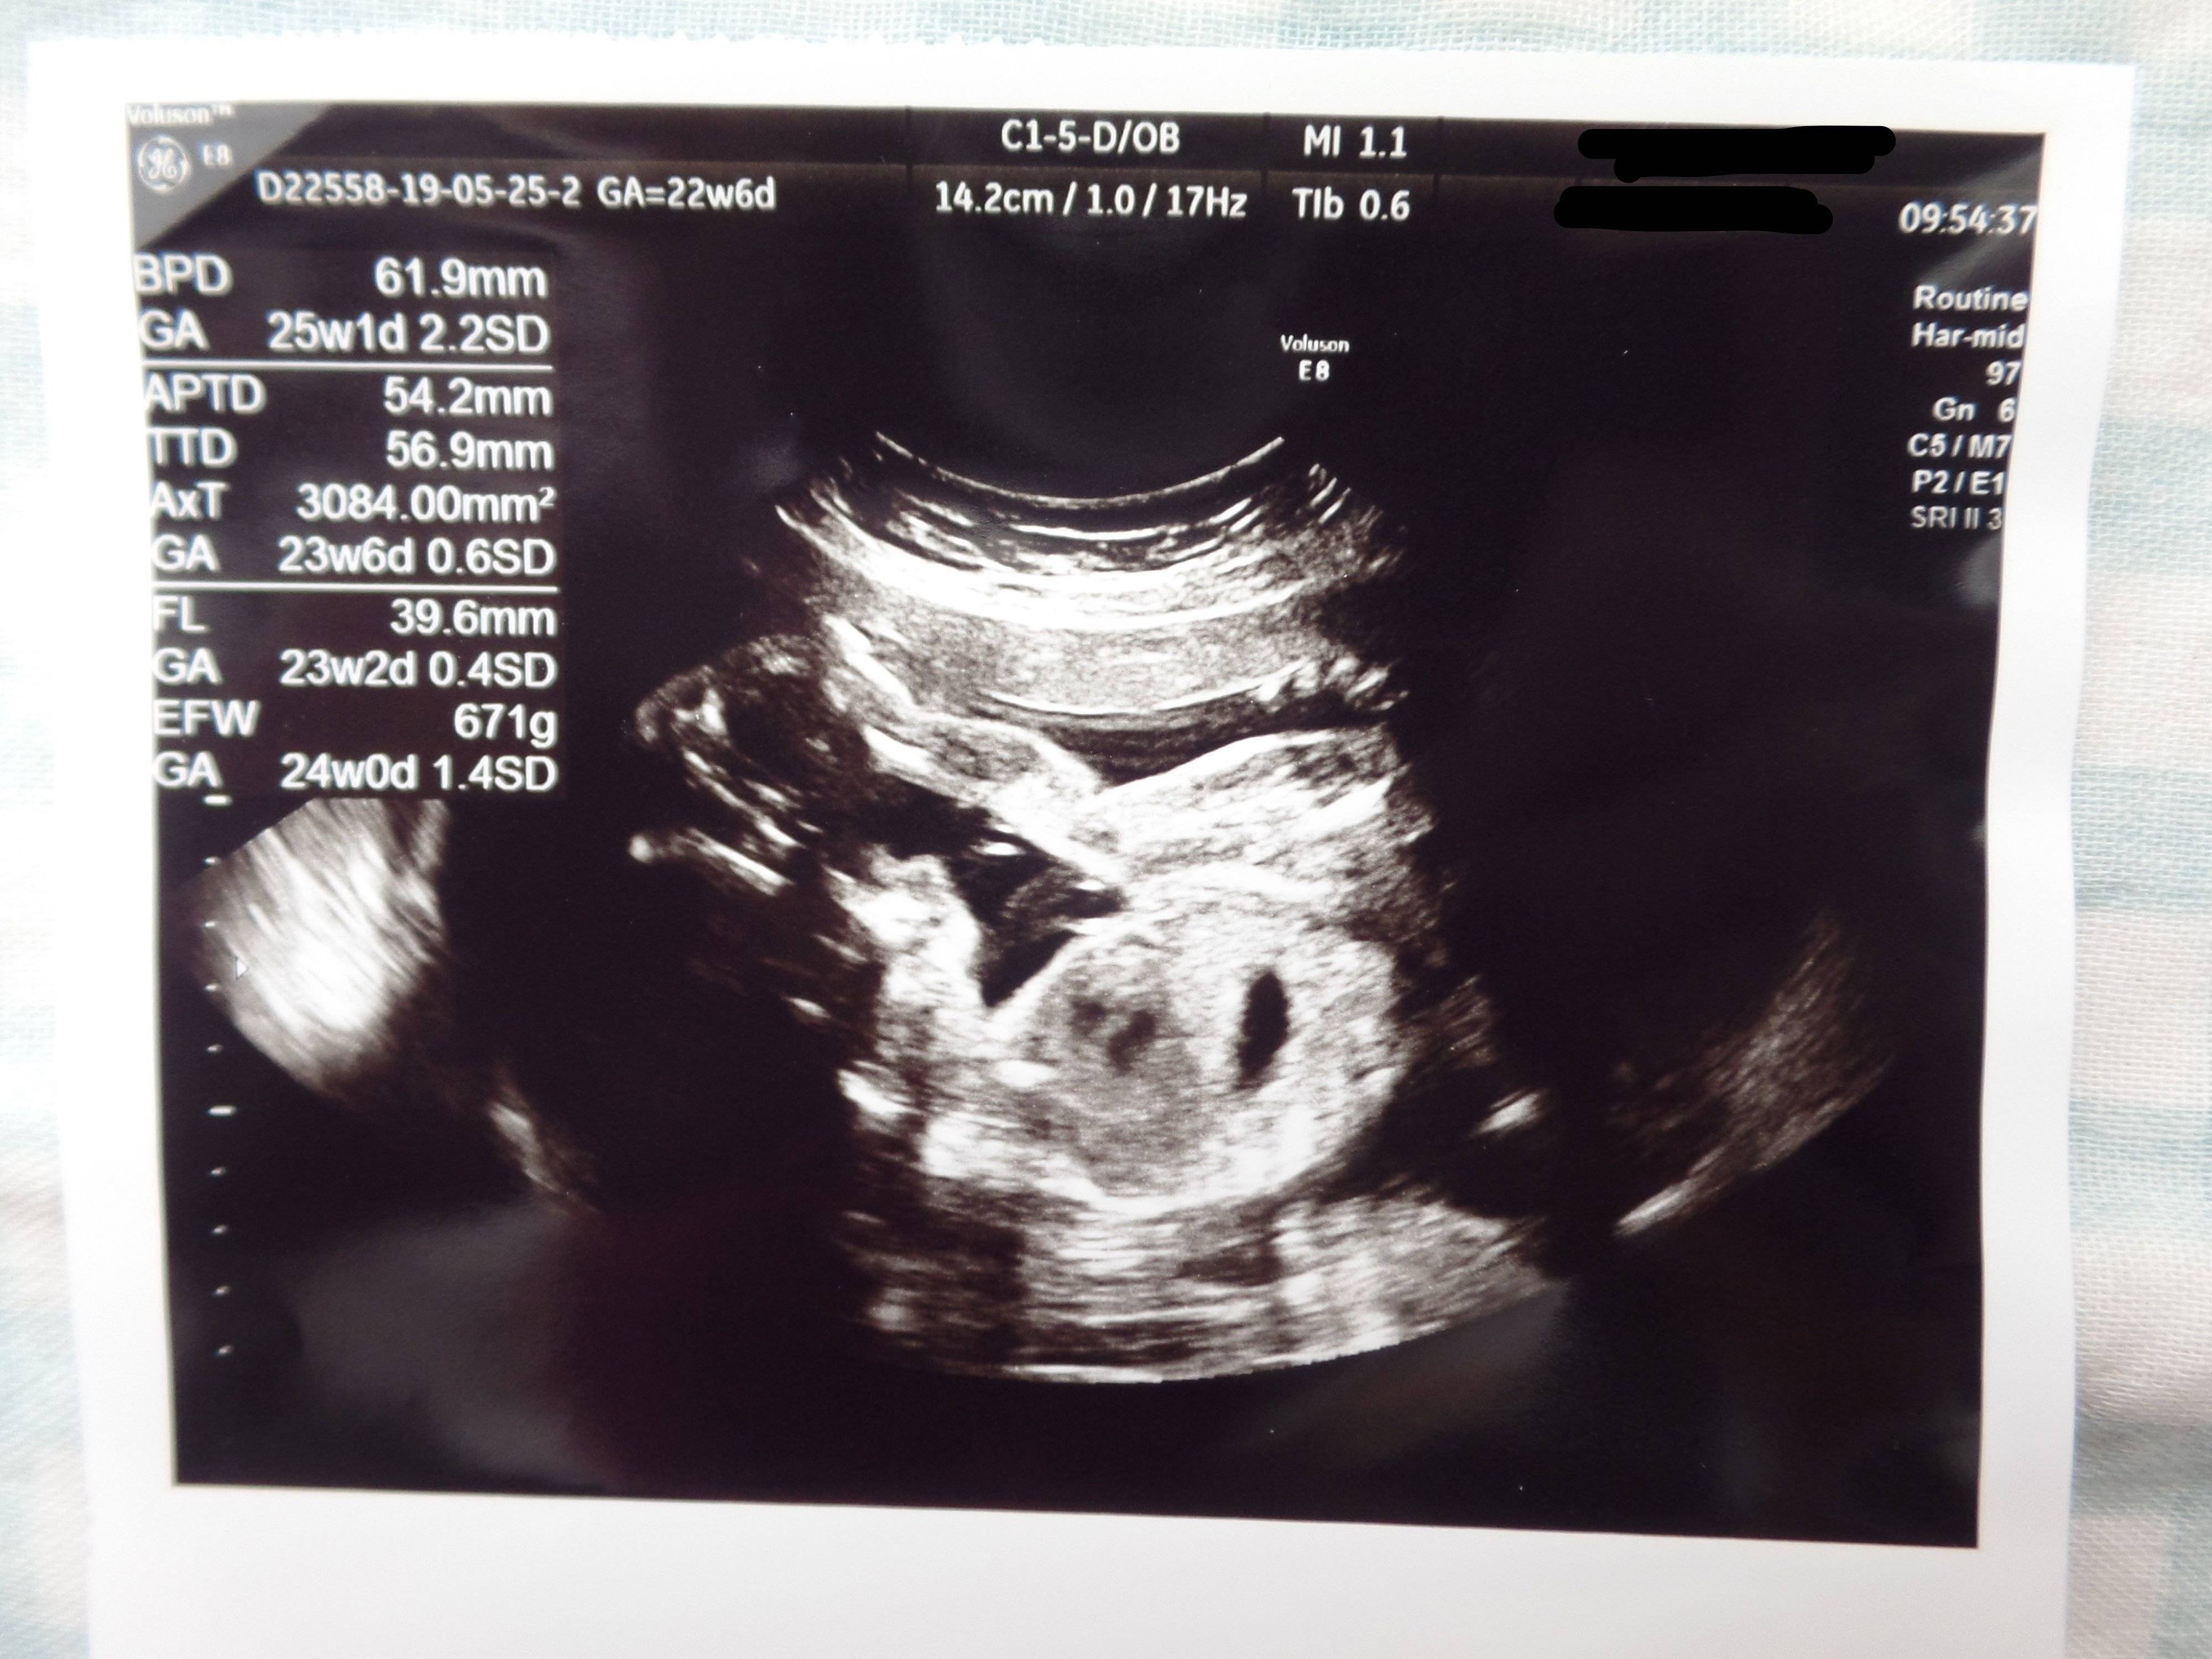

3. 多嚢胞性卵巣症候群(PCOS)から不妊治療を経て高齢出産! エコー写真で喜びを振り返る